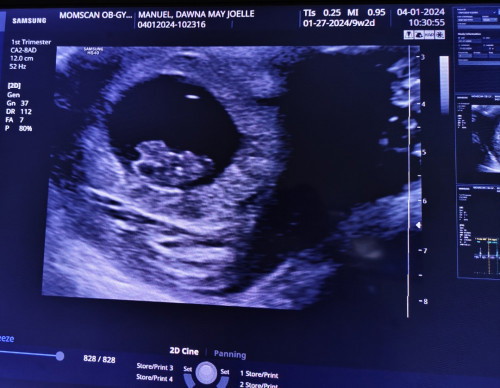

No More subchorionic hematoma

Nung una sobrang worried ako kasi meron akong sch. Ngayung 9weeks na si baby nawala na totally yung hemorrhage ☺️☺️